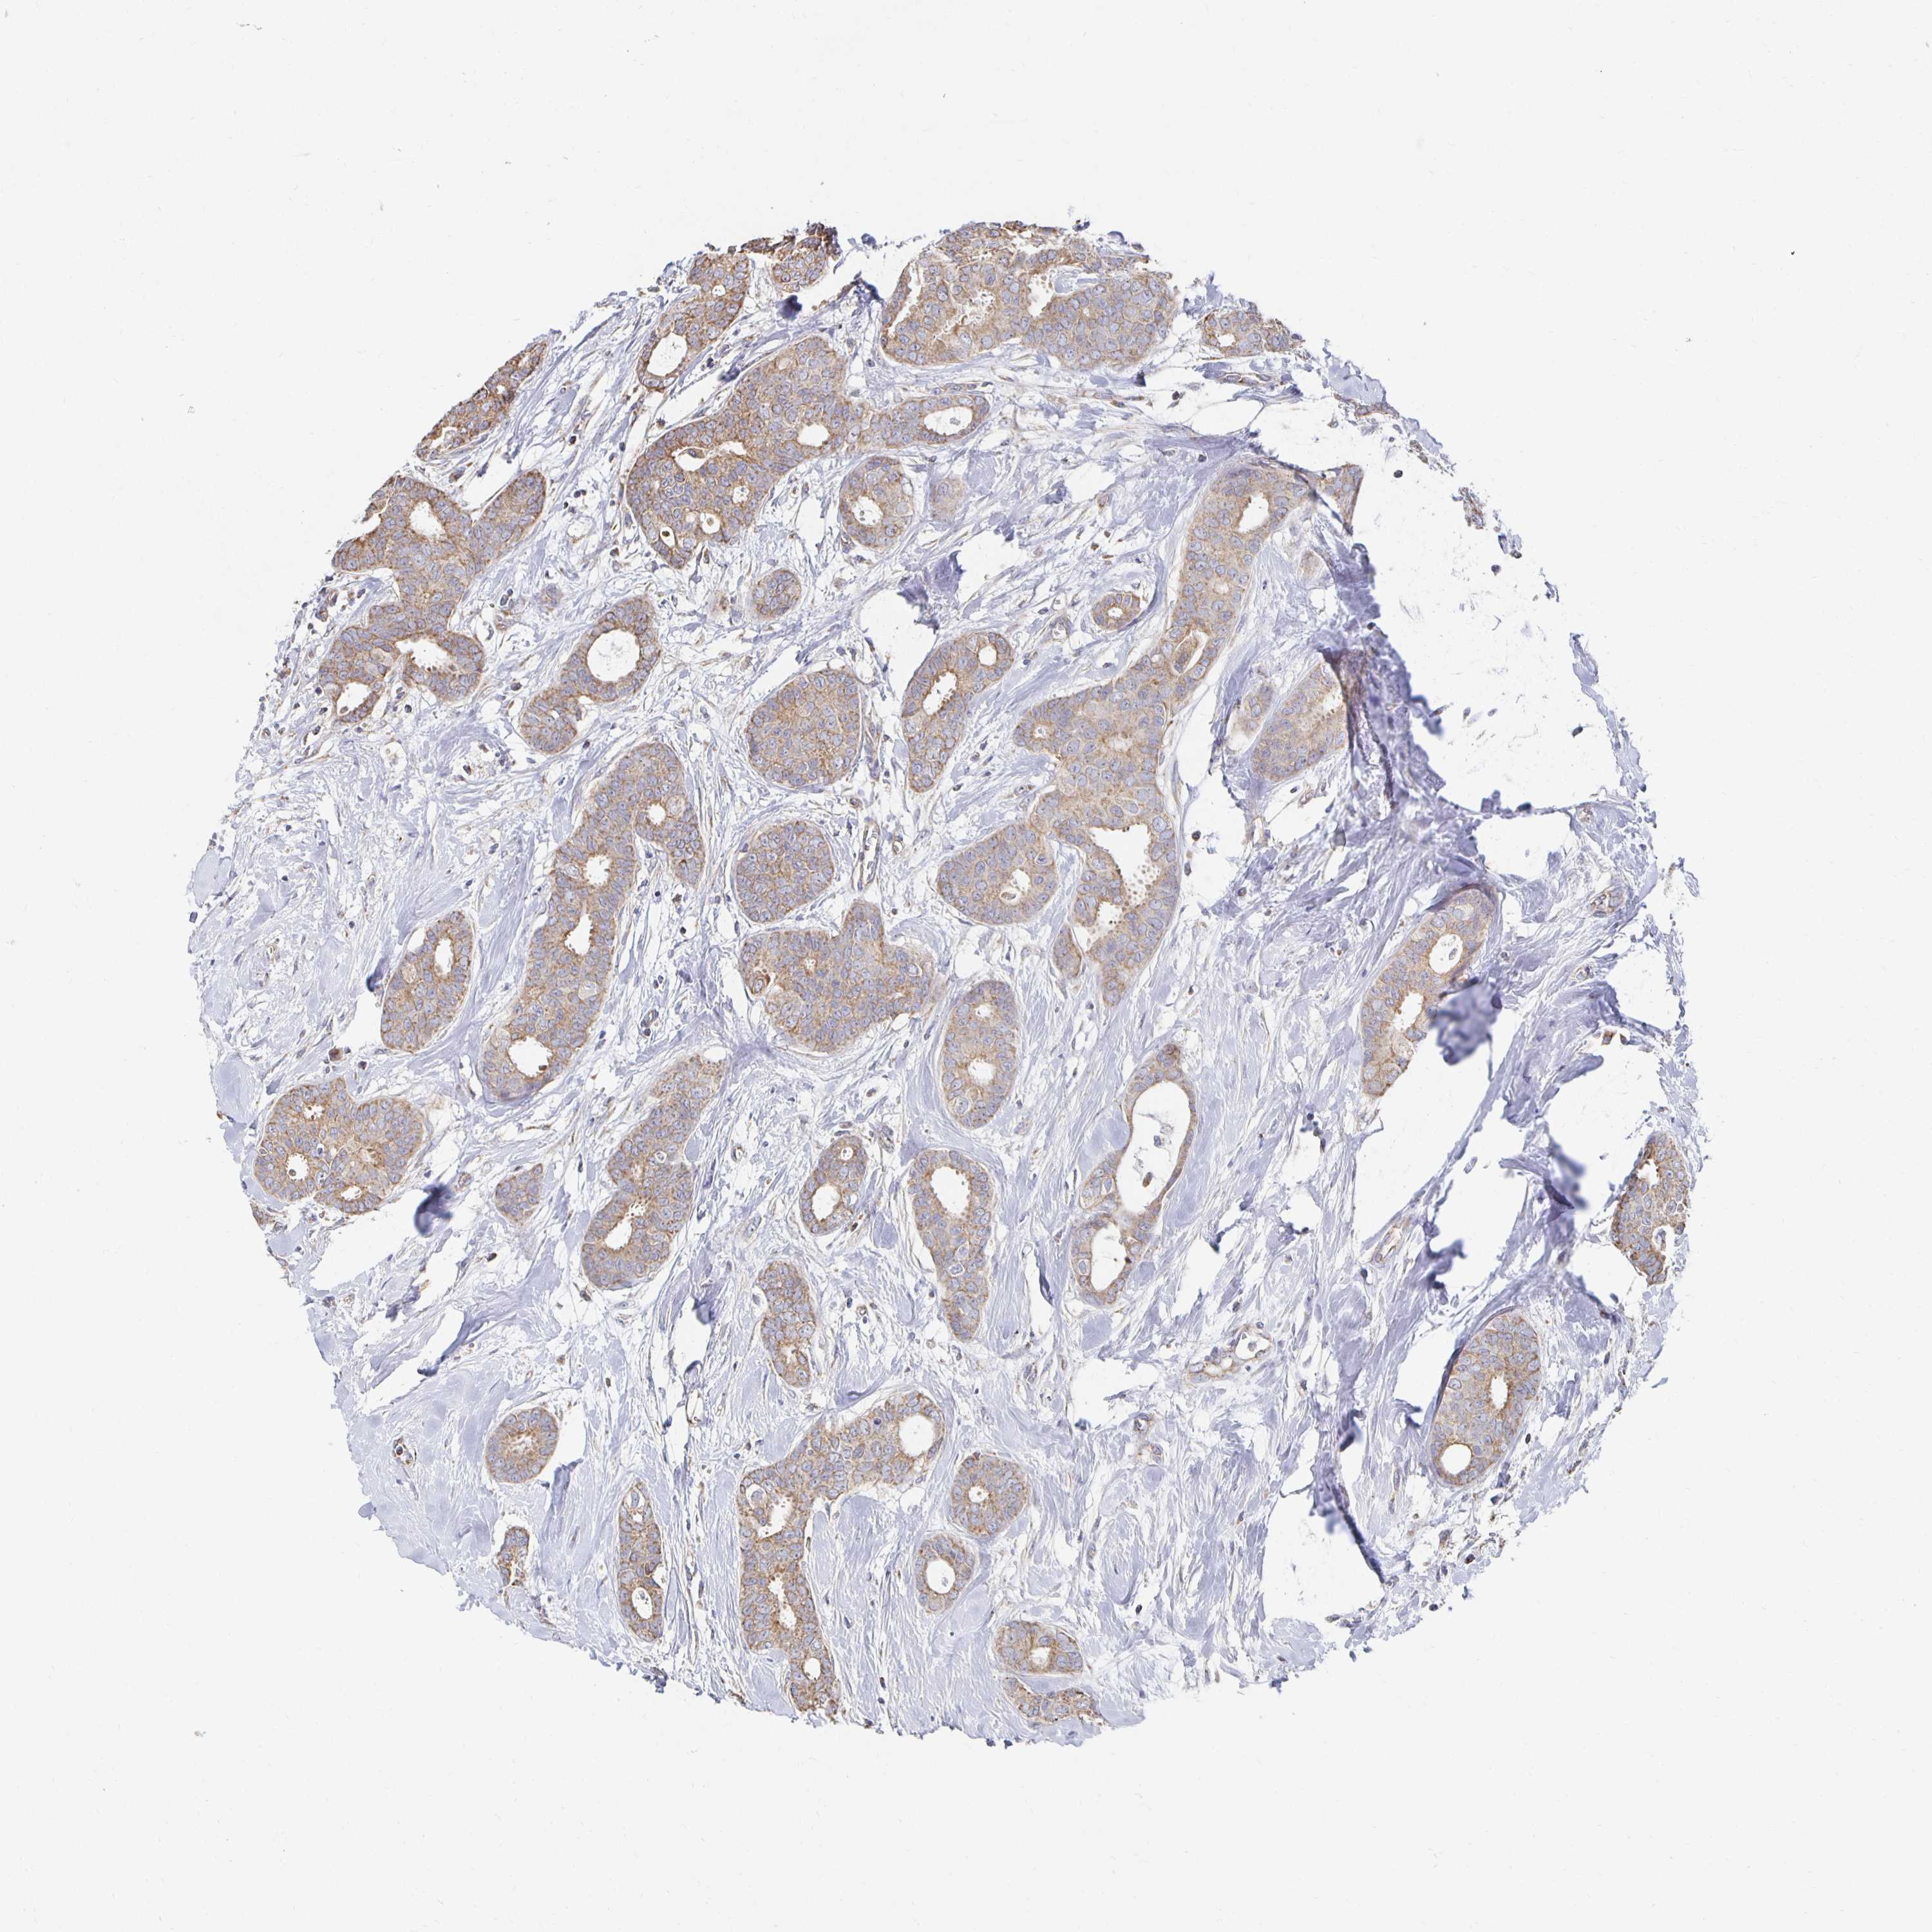

BRCA TCGA BRCA VALIDATION PROTEIN EXPRESSION

Breast cancer

Human cancer

Breast invasive carcinoma